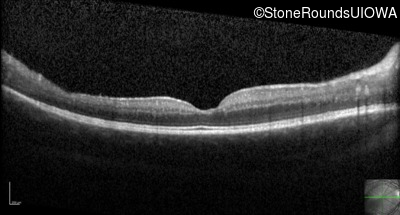

Optical Coherence Tomography - Right - 20/40 +2 sc

Exemplar / OCT Stack

OCT Stack